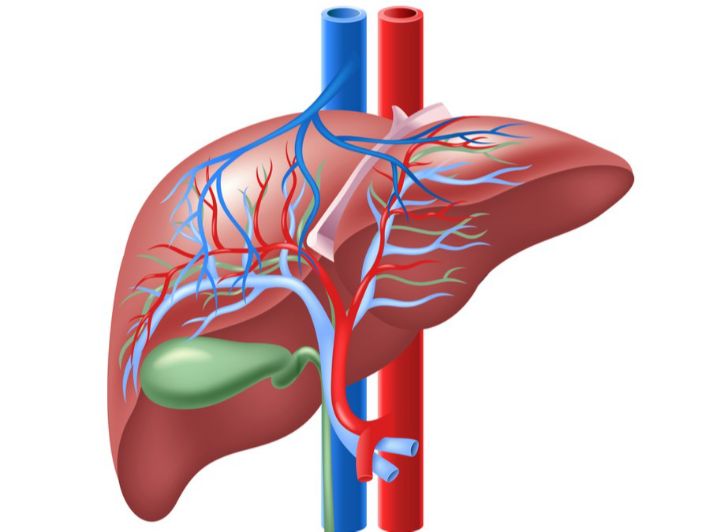

وكالات- الاقتصادي: يتمتع الكبد بقدرة عالية على التجدد بفضل بنيته، ولكن لهذه القدرة حدود معينة.